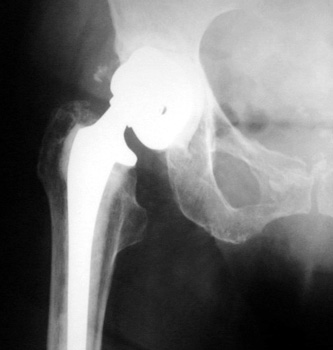

Very abnormal positioned cup. No comparison radiographs were available. Current radiographs demonstrates markedly tilted cup which has migrated laterally from pelvis.